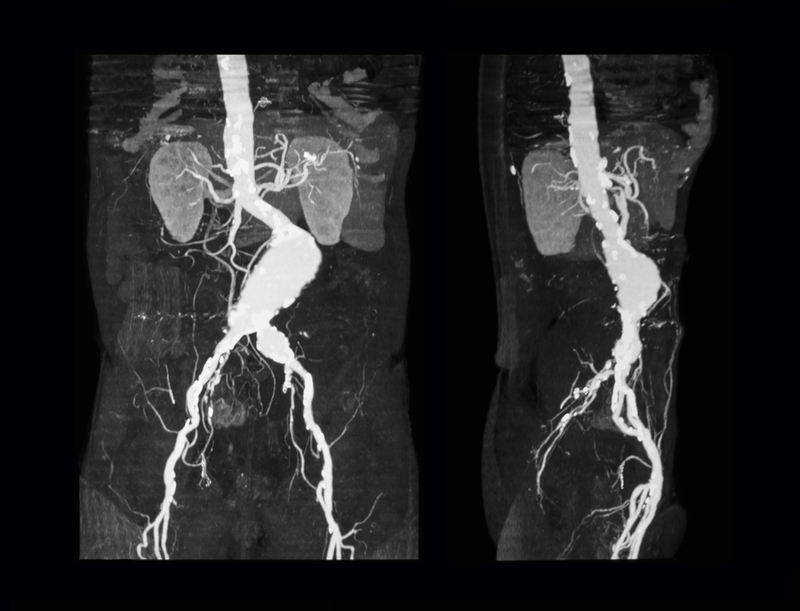

The abdominal aortic aneurysm is a swelling or ballooning that occurs in the major blood vessel (aorta) that supplies blood from the heart to the lower half of the body. It affects about 3 per cent of older Americans, most commonly men and smokers. The condition can cause fatal internal bleeding if the aneurysm grows large enough to burst. Small aneurysms frequently cause no symptoms and are often detected when an abdominal ultrasound or CT scan is performed for other reasons.

The JAMA study involved 254 patients with small aneurysms who were randomly assigned to take either 100 milligrams of doxycycline twice daily or a placebo for two years; CT scans performed at the beginning of the study and on follow-up found no differences in aneurysm growth between those who took the drug and those who took the placebo.